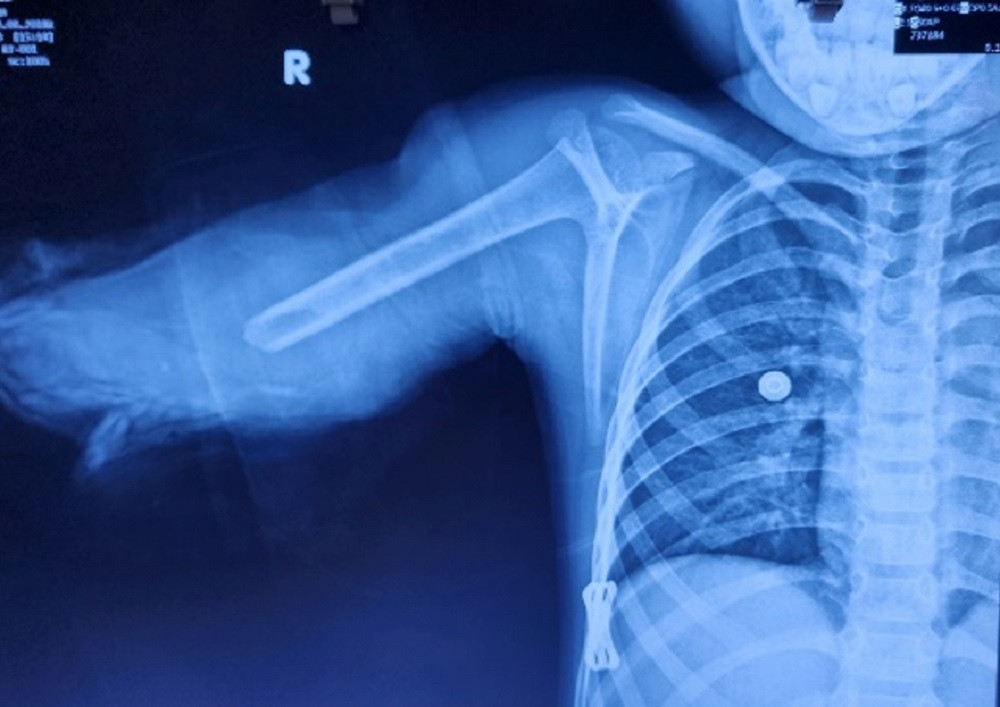

| Cánh tay phải của bệnh nhi bị đứt lìa, dập nát phức tạp trên hình ảnh kiểm tra (ảnh: BSCC) |

Bệnh nhi được chuyển cùng cánh tay đứt lìa đến bệnh viện địa phương sơ cứu, sau đó chuyển lên TPHCM cấp cứu. Tại Bệnh viện Chấn thương Chỉnh hình, qua thăm khám, bác sĩ ghi nhận, bệnh nhi trong tình trạng mất nhiều máu, vết thương đứt lìa dạng vặn xoắn ở 1/3 dưới cánh tay phải, gãy 2 xương cẳng tay.